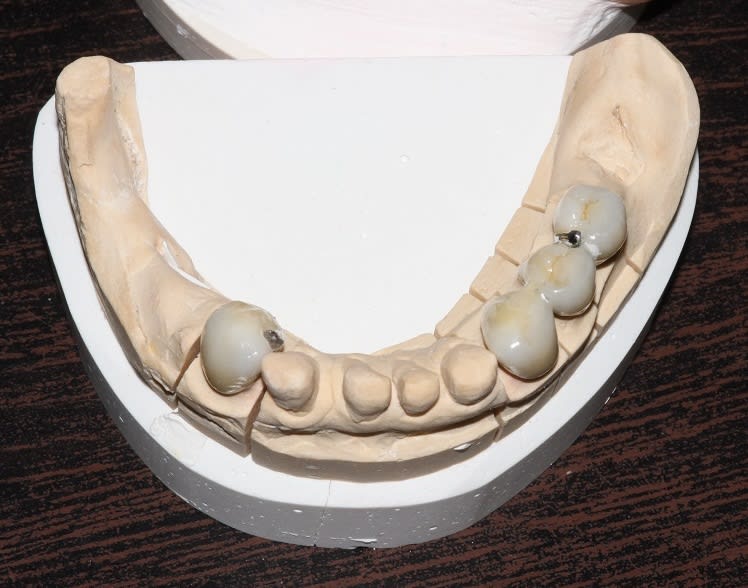

Donc entre temps, j'ai fini cette histoire, ça aura pris un peu moins de 3 mois, vacances et jours fériés compris.

Donc d'abord réalisation des céramiques du bas et du stellite...

A chaque fois on en profite pour rebosser les anatomies.

Img 4367 k06atf - Eugenol

13/06/2018 à 13h25

M'a embêté d'ailleurs ce stellite, il passait son temps à me l'éjecter, j'ai mis un moment à repérer la zone où le plancher lingual remontait pour le repousser, du détail mais bon.

Puis réalisation du postérieur haut, la 28 n'est toujours pas extraite, j'attends qu'elle égresse suffisamment pour la sortir sans anesthésie haha.

On voit qu'à force de modif, la ligne des bords libres est trop basse, la courbe de wilson trop prononcée pour un homme de 60 piges.